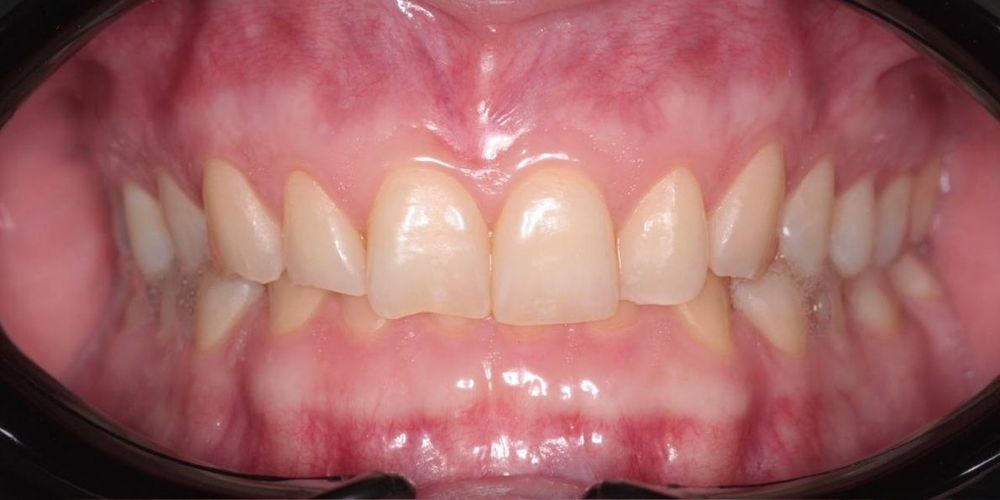

Пациент обратился с проблемой глубокого прикуса: верхние зубы сильно перекрывали нижние. Это не только портило улыбку, но и создавало дискомфорт при жевании, ускоряло стираемость эмали и нагружало височно-нижнечелюстной сустав.

- глубокий прикус исправлен

- зубы выровнены, улыбка стала гармоничной и красивой